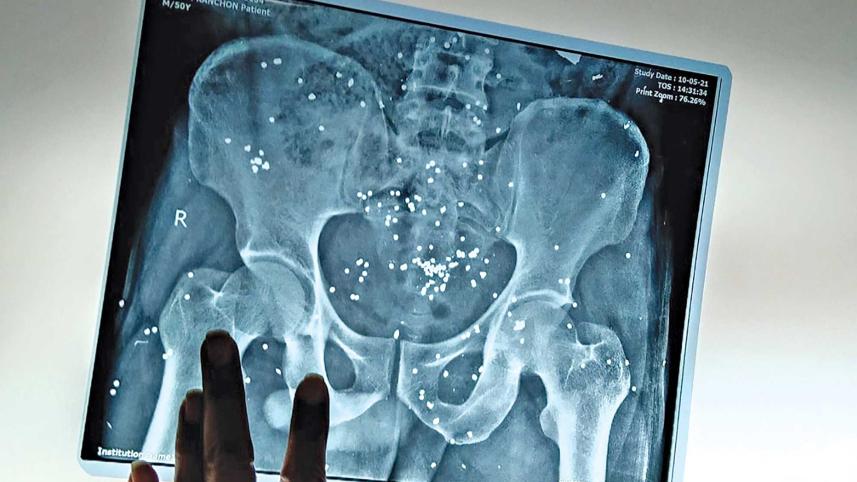

On May 10 this year, workers of an RMG factory owned by the conglomerate Ha-Meem Group took to the streets to demand Eid holidays. Instead of meeting their perfectly legitimate demands, law enforcement was called in, and it is now evident that the police used disproportionate force. Kanchon—one of 12 workers who were injured that day—was shot with pellet guns at point blank range. Later, some 101 pellets were removed from his intestines. A large part of his intestines and lower abdomen had to be removed. Now he needs gut reconstruction surgery, but doctors are hesitant to operate due to his severely malnourished condition. The only breadwinner of his seven-member family, Kanchon will not be able to do any strenuous work for the rest of his life.